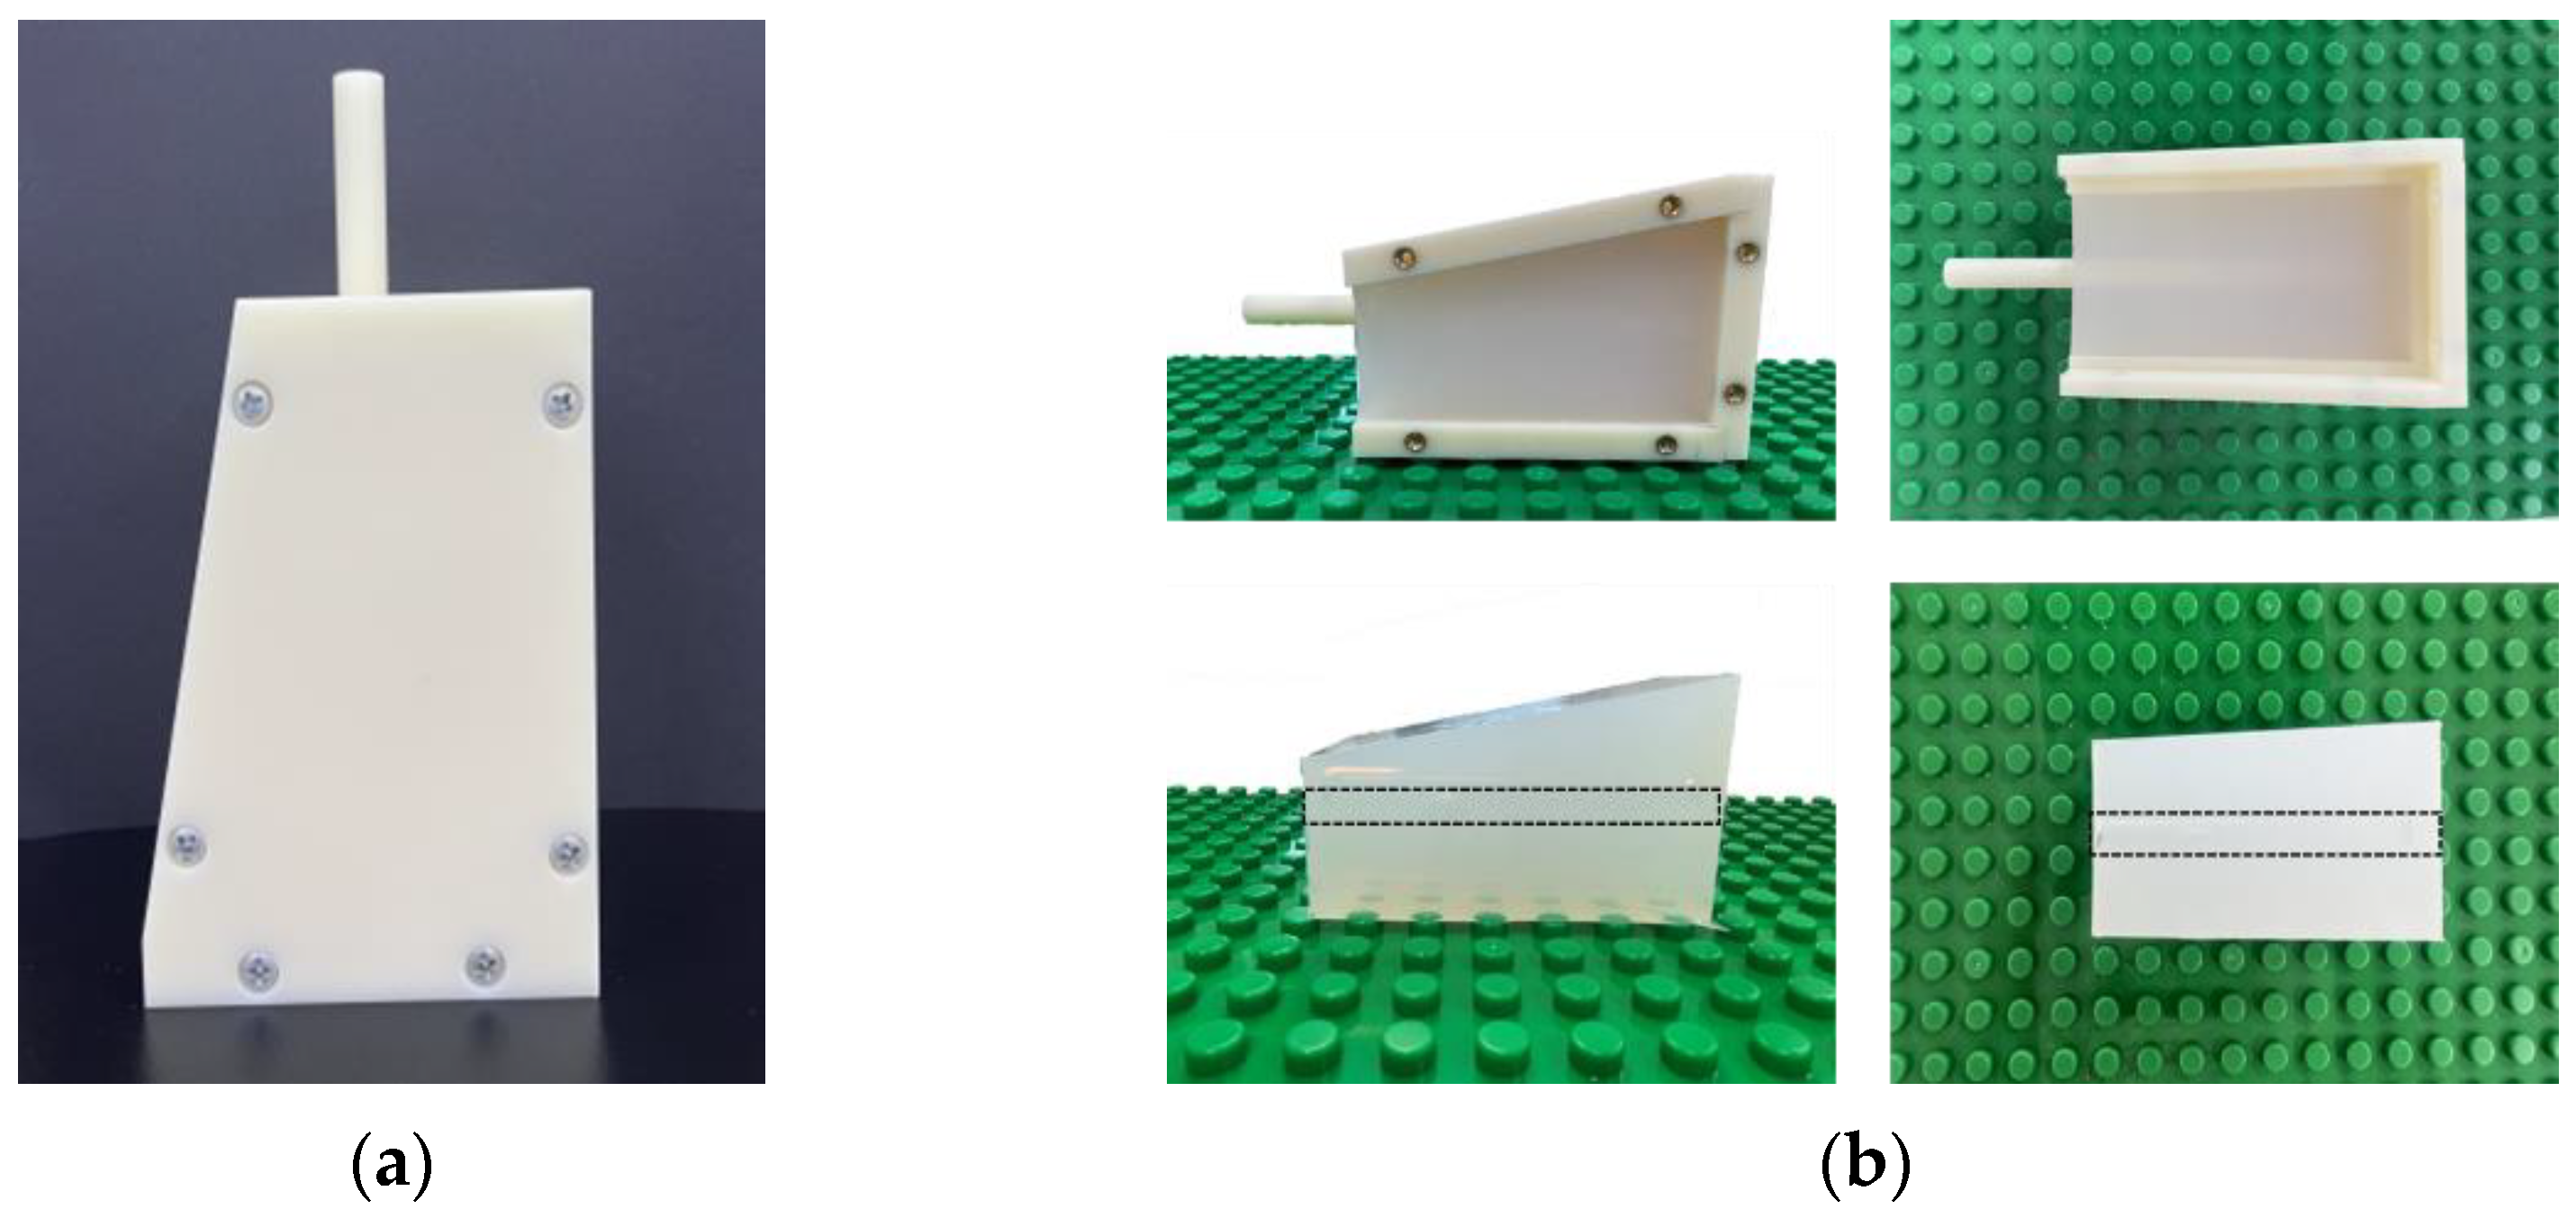

2.1. Vessel-Mimicking Phantom

2.2. Dopppler Ultrasound Training Phantom

3.1. Vessel-Mimicking Phantom